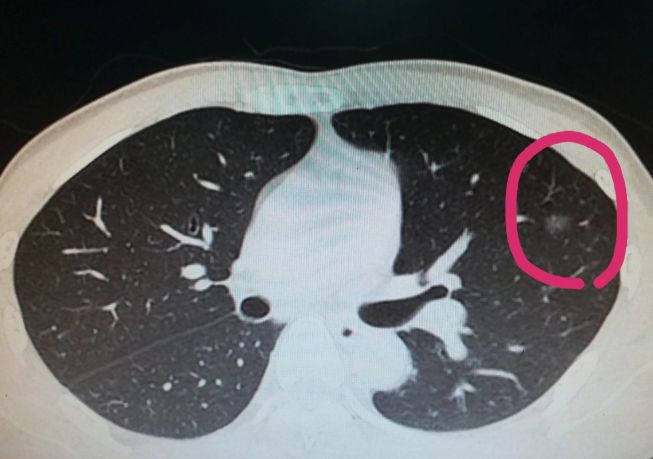

现如今,伴随着肺部CT检查的普及,肺结节的检出率年年升高。 身边很多朋友看到了检查报告里面说有肺结节,都非常惶恐自己得了肺癌。 其实大部分的肺结节都是良性的,占到总病例的90%左右。这些良性结节多是炎症、感染、肺纤维增殖、肺钙化,因此查出肺结节不用过分担心。 记住以下这些内容,如果CT检查发现肺结节,我们可以自己先对照一下片子和报告,了解一二。 越大的肺结节,考虑恶性的可能性就越大,结合肺结节的密度,关于大小有三个主要分水岭,即15mm,8mm,5mm。 一般来说,指南中低于5mm的都是低危结节,而在实际临床中,10mm以下的结节良性的可能性都很大,当然我们也发现6mm的恶性结节,这样的病例很少。 一般结节边缘光滑的是良性的可能性大(并非全部),出现花瓣一样分叶的,恶性的比率就是增高,而分叶且又出现毛刺的恶性可能性就比较大了,恶性可能性最大的是分页,毛刺,而毛刺又短又细。 肺结节出现的两肺上叶的恶性可能性大,尤其是右肺上叶。 出现的中下肺叶的良性可能性大。 肺结节的横断面10%以上出现钙化的,良性概率大,一般恶性结节出现钙化的几率比较小。 半实性结节的恶性可能高于磨砂玻璃结节高于实性结节。 自己怎么看呢?就是看结节的样子。 实性结节像一个鸡蛋,中间是蛋黄(实的),周围是蛋清(薄纱状); 结合结节的大小,直径大于15mm的实性结节和直径大于8mm的半实性结节为高危结节。 对比两次CT检查结果,看肺结节的生长速度,我们以6个月为例,如果六个月内肺结节的长大过快,大概一倍左右,那么恶性可能性大; 如果增长缓慢,那么良性可能性大;如果缩小或者消失了,那就可能是炎症。

02 边缘形态